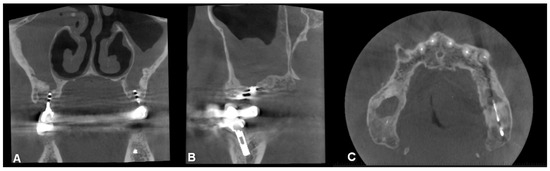

Figure 6. CBCT image of unilateral maxillary sinusitis and oro-antral fistula with the characteristic radiological image of fungal infection, which radiologically mimics foreign bodies ((A): coronal, (B): axial, (C): sagittal view).